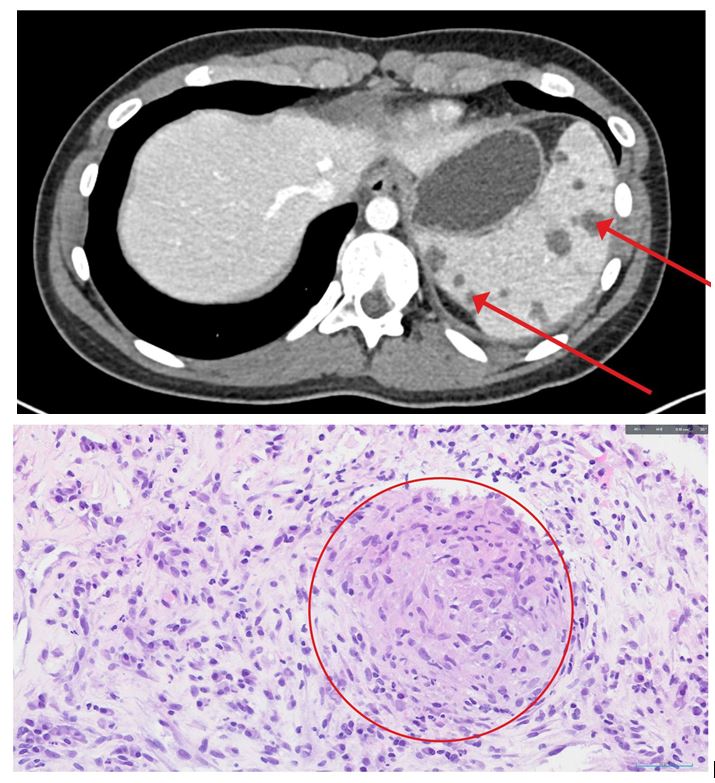

Presentamos el caso de una mujer de 15 años diagnosticada de sarcoidosis esplénica aislada durante su ingreso hospitalario por fiebre de origen desconocido. El estudio anatomopatológico reveló la presencia de un granuloma esplénico no caseificante y de granulomas necrotizantes. La respuesta clínica y radiológica observada tras el tratamiento con corticosteroides reforzó el diagnóstico. La sarcoidosis debería considerarse en el diagnóstico diferencial de fiebre prolongada, incluso en pacientes jóvenes sin sintomatología respiratoria.